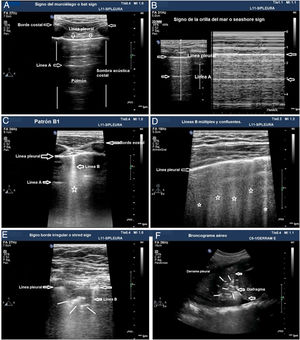

Los patrones de aireación de cada región pulmonar son (fig. 2):

Patrón A: patrón típico de aireación normal. Línea pleural con deslizamiento conservado, presencia de líneas A y ≤ 2 líneas B bien espaciadas (fig. 2A y B).

Patrón B1: presencia de más de dos líneas B bien espaciadas, difusas en las distintas áreas del tórax, denominadas septal rockets (fig. 2C).

Patrón B2: líneas B confluentes separadas entre ellas por ≤ 3 mm (ground-glass rockets) debido a pérdida más severa de pulmón aireado (fig. 2D).

Patrón C: consolidación pulmonar, que sugiere pérdida importante de pulmón aireado por acúmulo de líquido y/o células en los alveolos. La consolidación puede detectarse en cualquier punto del hemitórax, pero la aplicación del transductor en el punto PLAPS detecta el 95% de los casos (fig. 2E y F).

Patrones de aireación pulmonar. A) Patrón típico de aireación normal (perfil A en el protocolo BLUE) mostrando imagen en 2D. B) Patrón A en modo M. C) Patrón B1. D) Patrón B2. E) Consolidación pulmonar (perfil C en el protocolo BLUE), mostrando signo del borde irregular o shred sign. F) Broncograma aéreo. A, B, C, D y E: estudio con sonda lineal; F: sonda convex.